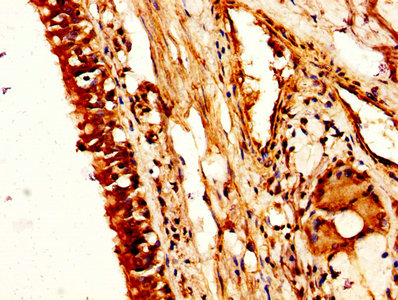

IHC image of CSB-PA016146HA01HU diluted at 1:200 and staining in paraffin-embedded human small intestine tissue performed on a Leica BondTM system. After dewaxing and hydration, antigen retrieval was mediated by high pressure in a citrate buffer (pH 6.0). Section was blocked with 10% normal goat serum 30min at RT. Then primary antibody (1% BSA) was incubated at 4°C overnight. The primary is detected by a biotinylated secondary antibody and visualized using an HRP conjugated SP system.